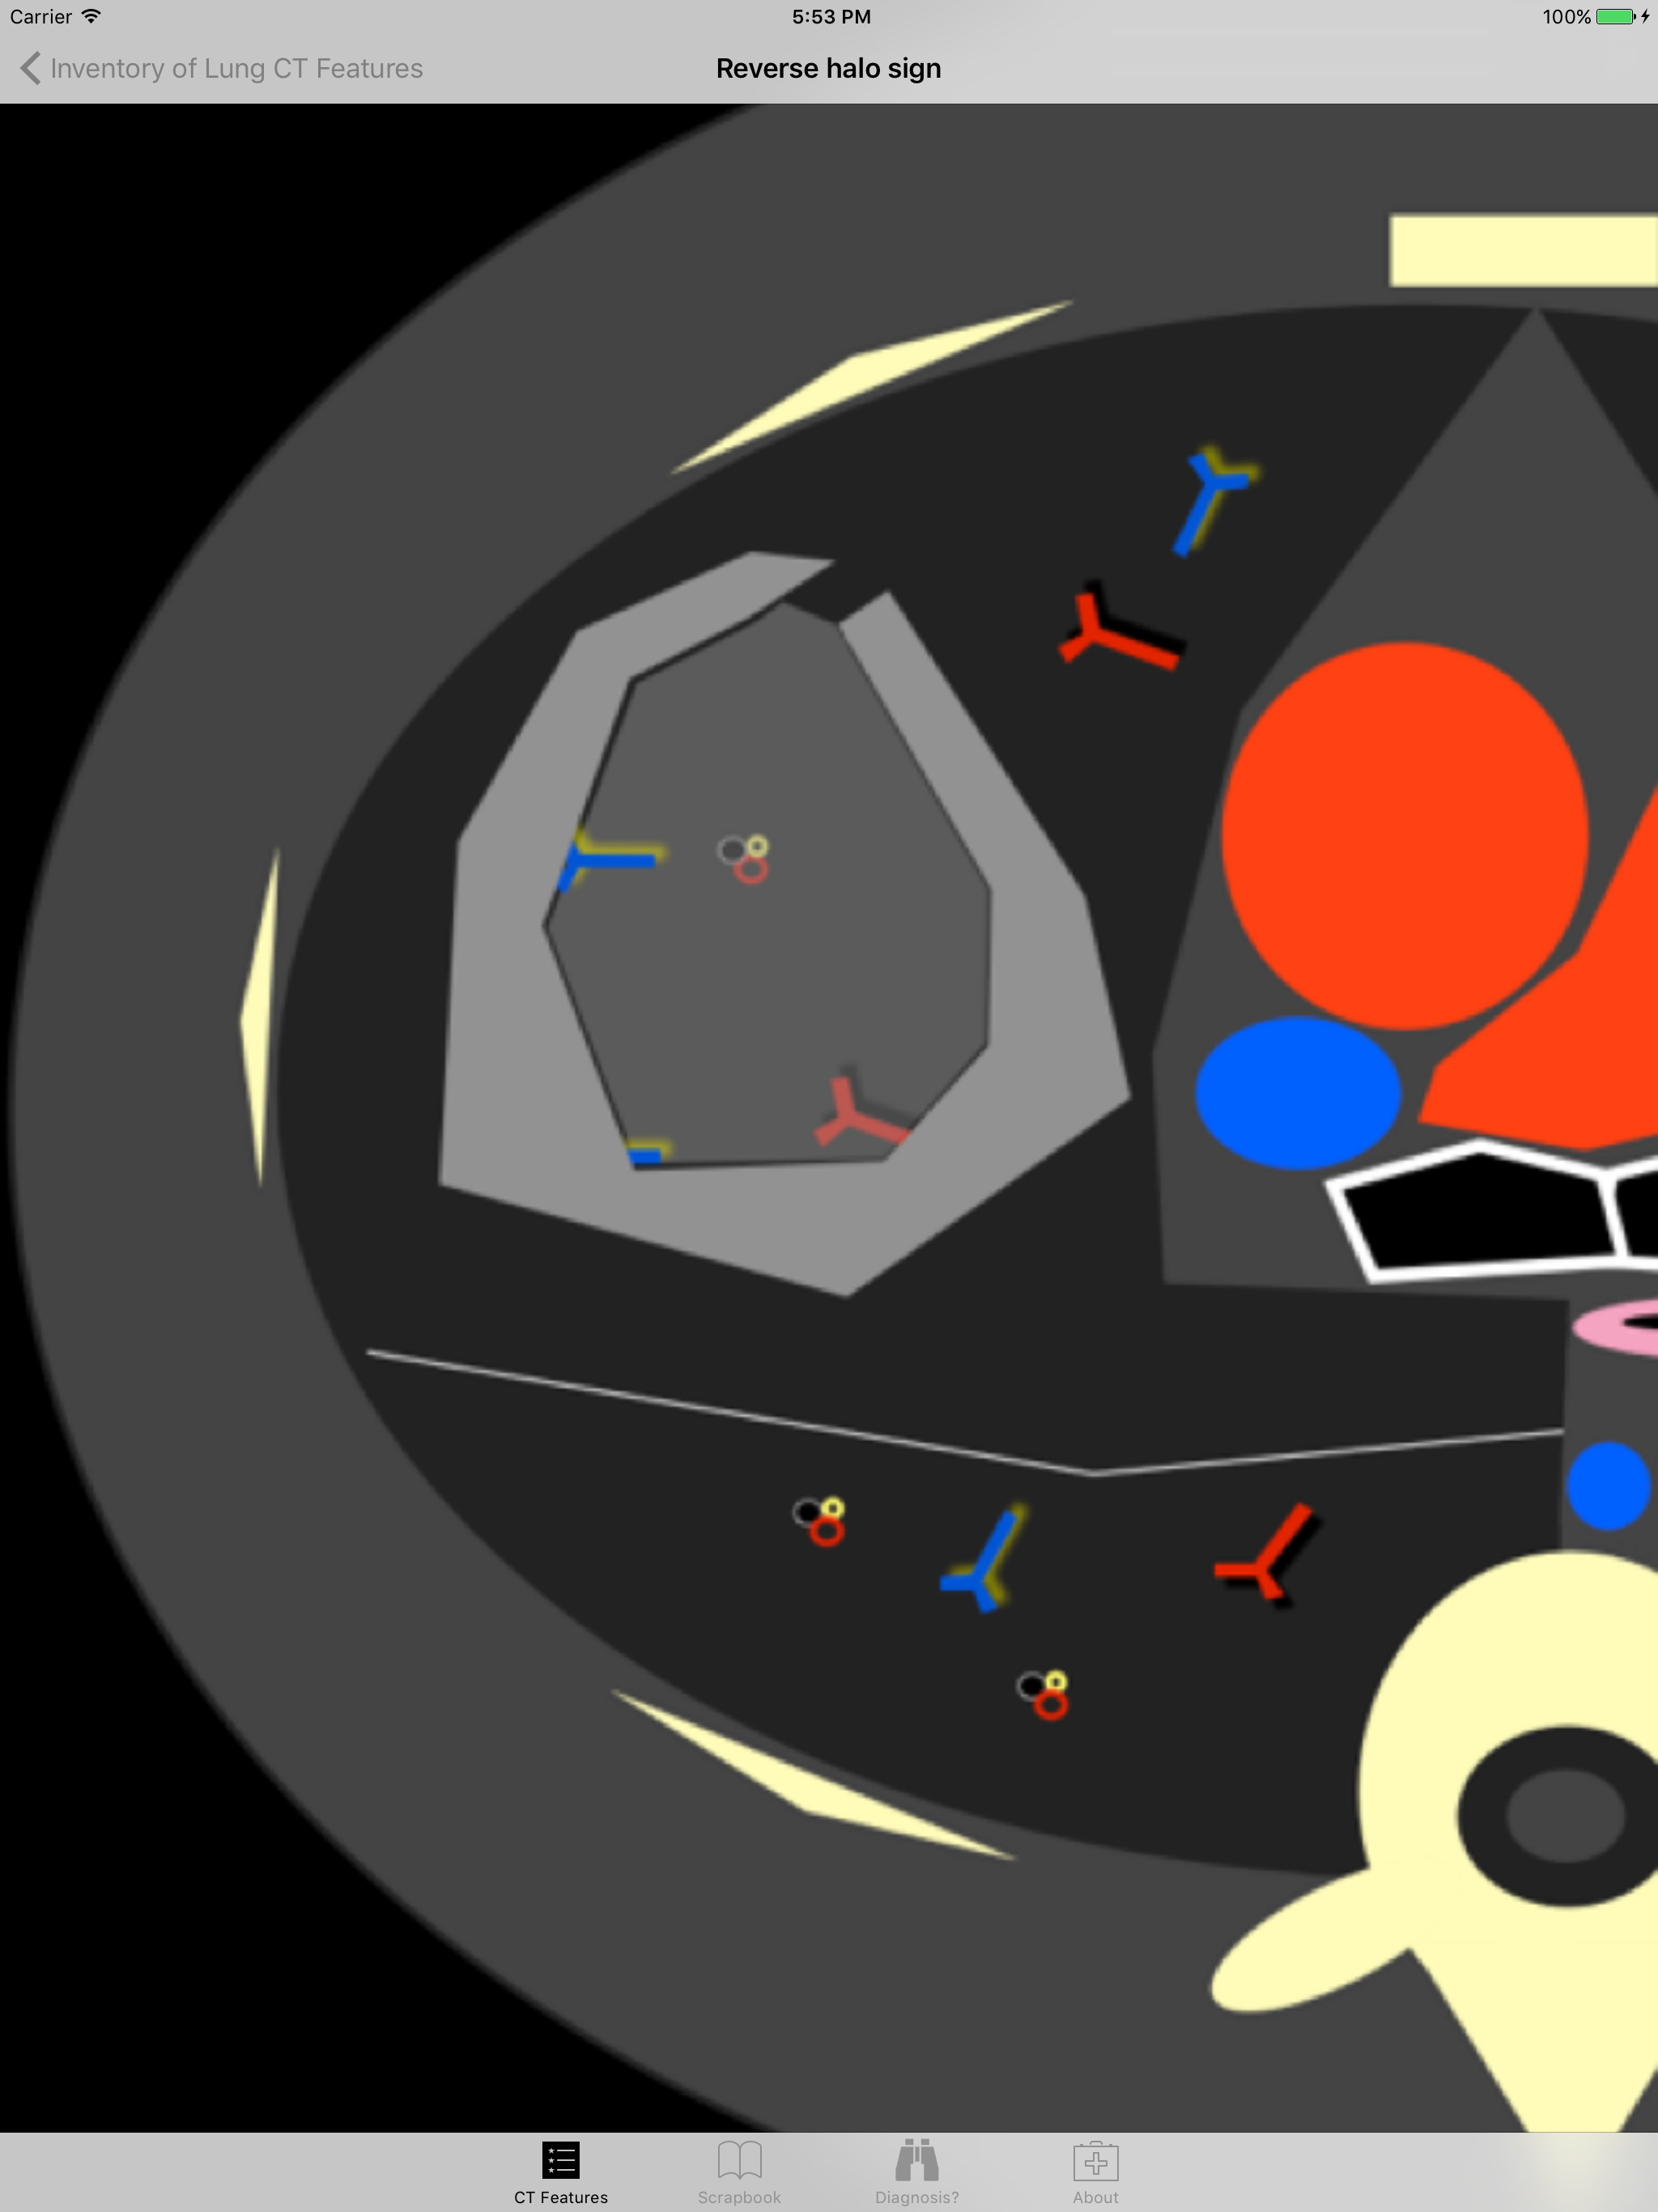

Introducing the Lung CT Field Guide app, an excellent resource for a wide-range of physician specialists, in particular radiologists and pulmonologists. One of the critical steps in interpreting a lung CT is identifying and appropriately describing imaging findings in the lung. Review and explore lung CT images and color graphic illustrations of the fundamental patterns of lung disease on CT. Play with an experimental diagnosis engine that will try to suggest a differential diagnosis list to consider with any number and combination of lung CT findings! Includes over 100 carefully curated CT images and color graphic illustrations. An invaluable resource for staff physicians, fellow physicians, resident physicians, and medical students at an unmatched price. Browse · Over 60 prototypical lung CT images, organized by: increased attenuation findings, decreased attenuation findings, miscellaneous findings, craniocaudal distribution, and axial distribution · Nearly 60 color graphic illustrations of prototypical lung CT imaging features Discover · Experimental diagnosis engine takes your lung CT observations and will try to suggest a differential diagnosis list to consider - for educational purposes only Requirements · Requires a device with iOS 7 or later